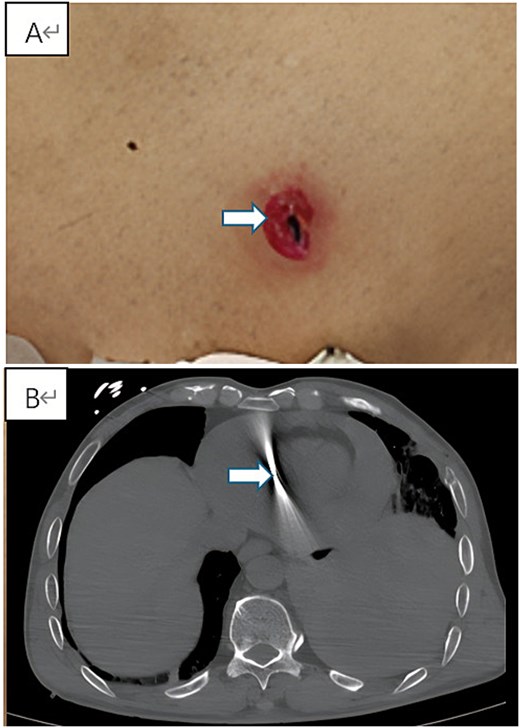

Upon arrival, physical examination under norepinephrine infusion showed a blood pressure of 97/67 mmHg, a heart rate of 121 beats per minute, and a respiratory rate of 30 breaths per minute. A 0.5 × 1.0 cm spindle-shaped wound (Fig. 1A) was observed on the left anterior chest wall, with a small amount of bloody discharge. Breath sounds were diminished over the left lower lung, heart sounds were distant, and cardiac borders were enlarged. An urgent repeat chest CT demonstrated an irregular dense shadow with radial artifacts within the heart, suggestive of a cardiac foreign body, accompanied by moderate pericardial hemorrhage and moderate-to-large left hemothorax with associated atelectasis (Fig. 1B). Echocardiography confirmed a 12.5 × 11.8 mm hyperechoic mass in the pericardial cavity along with moderate pericardial effusion. Given the critical condition, an emergency thoracotomy was performed following evaluation by the cardiac surgery team (Video 1).

Preoperative clinical and imaging findings. (A) Photograph showing the spindle-shaped entry wound (0.5 × 1.0 cm) on the left anterior chest wall (indicated by arrow). (B) Axial view of contrast-enhanced chest CT revealing the metallic foreign body within the cardiac silhouette with radiopaque artifacts, accompanied by pericardial effusion and left hemothorax.